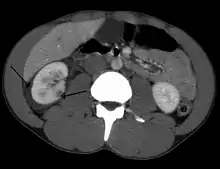

Abdominal trauma resulting in a right kidney contusion (open arrow) and blood surrounding the kidney (closed arrow) as seen on CT

A large hematoma (closed arrow) of the left kidney (open arrow)

The kidneys may also be injured; they are somewhat but not completely protected by the ribs.[6] Kidney lacerations and contusions may also occur.[13] Kidney injury, a common finding in children with blunt abdominal trauma, may be associated with bloody urine.[13] Kidney lacerations may be associated with urinoma or leakage of urine into the abdomen.[4] A shattered kidney is one with multiple lacerations and an associated fragmentation of the kidney tissue.[4]